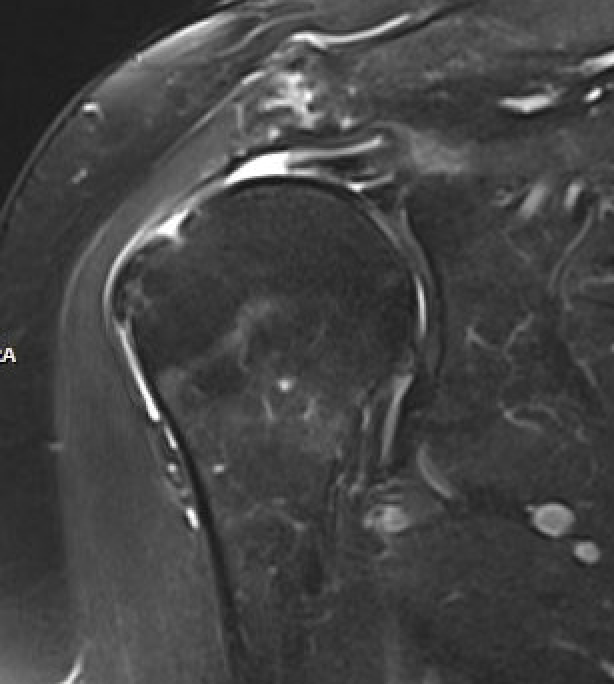

MRI

Look for

- supraspinatus / infraspinatus / subscapularis / long head of biceps pathology

- partial verus full thickness

- size of tear in coronal and sagittal planes

- retraction

- atrophy / fatty infiltration

Full thickness rotator cuff tears

Partial bursal sided tear Partial articular sided tears

Large full thickness tear of supraspinatus and infraspinatus tendon - retracted to midhumeral head